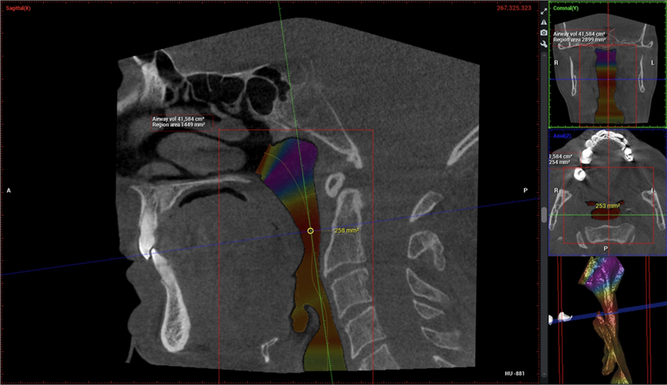

Cone-beam computed tomography (CBCT) is a specialized imaging system that captures detailed 3-D views of the teeth, jaws, sinuses, and airway in a single scan. Unlike traditional 2-D dental X-rays, which flatten complex anatomy, CBCT allows clinicians to view structures from multiple angles and at a true 1:1 scale.

CBCT is widely used in dentistry and medicine to evaluate airway size, jaw development, impacted teeth, and skeletal relationships:

For children, this is especially important. CBCT imaging can help identify narrow airways, restricted jaw growth, and anatomical contributors to mouth breathing and sleep-disordered breathing. Early identification allows for conservative, growth-guided care during childhood—often reducing the need for more invasive treatment later in life.

- Visualize airway volume and shape

- Identify areas of airway restriction

- Evaluate jaw position and growth patterns